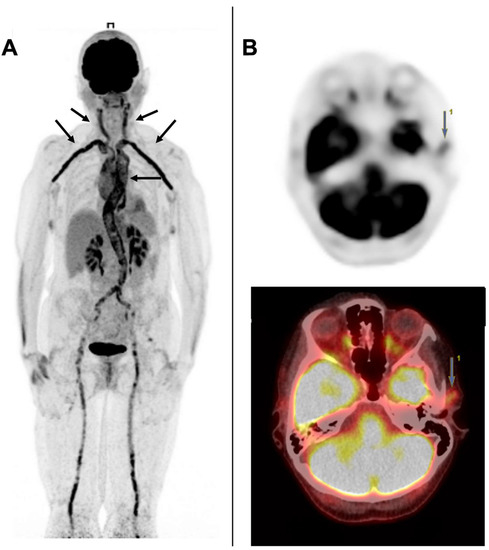

A Young Patient Presenting with Dilated Cardiomyopathy and Renal Infarction during Treatment with Isotretinoin: Mere Coincidence or Serious Side Effect of a Drug Commonly Used in Adolescence?

Isotretinoin or 13-cis-retinoic acid (RA) is one of the most effective and widely used drugs for the treatment of severe acne vulgaris. Despite being deemed safe, no definite consensus has been reached on the cardiovascular risk of RA derivatives. We report a case [...] Read more.

Isotretinoin or 13-cis-retinoic acid (RA) is one of the most effective and widely used drugs for the treatment of severe acne vulgaris. Despite being deemed safe, no definite consensus has been reached on the cardiovascular risk of RA derivatives. We report a case of heart failure due to dilated cardiomyopathy (DCM) and concomitant renal infarction occurring after 5 months of isotretinoin use in a previously healthy 18-year-old male. The patient, with a history of acne vulgaris, presented to our emergency department with left iliac fossa pain and effort dyspnea. A trans-thoracic echocardiogram showed DCM and severely reduced left ventricle ejection fraction (LVEF: 29%). During hospitalization, a total body computed tomography (CT) showed an ischemic lesion in the left kidney. Ischemic, autoimmune, infective, and heritable causes of DCM were ruled out. Cardiac magnetic resonance (CMR) evidenced LV circumferential mid-wall late gadolinium enhancement. Heart failure therapy was promptly started and up-titrated, but only poor LVEF improvement was detected overtime. Our case aims to raise awareness on rare life-threatening cardiovascular events possibly associated with isotretinoin use. To the best of our knowledge, this is the first described case of renal thromboembolism and severe DCM leading to implantable cardioverter-defibrillator (ICD) implantation occurring during isotretinoin treatment. Full article